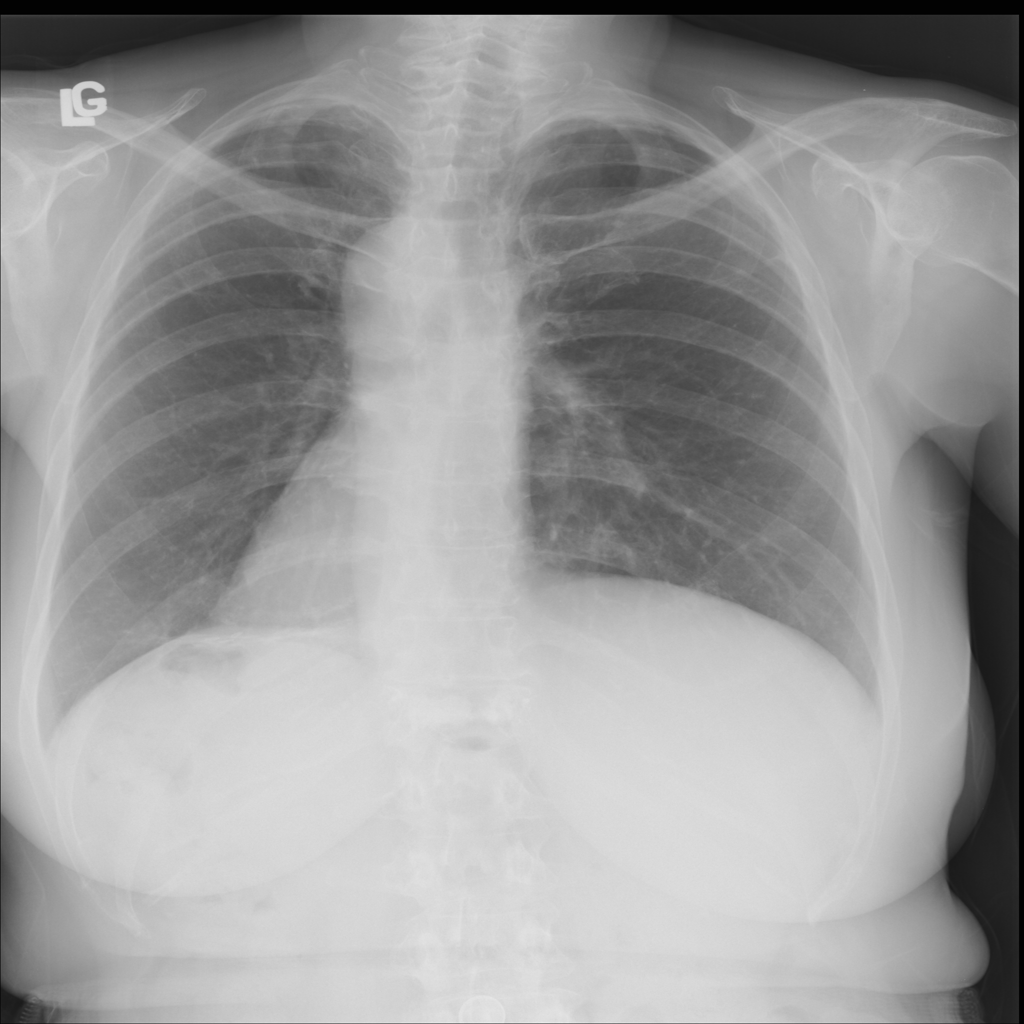

PAT-B625 · IMG-009Atelectasis

PAT-B625 · IMG-009

PA